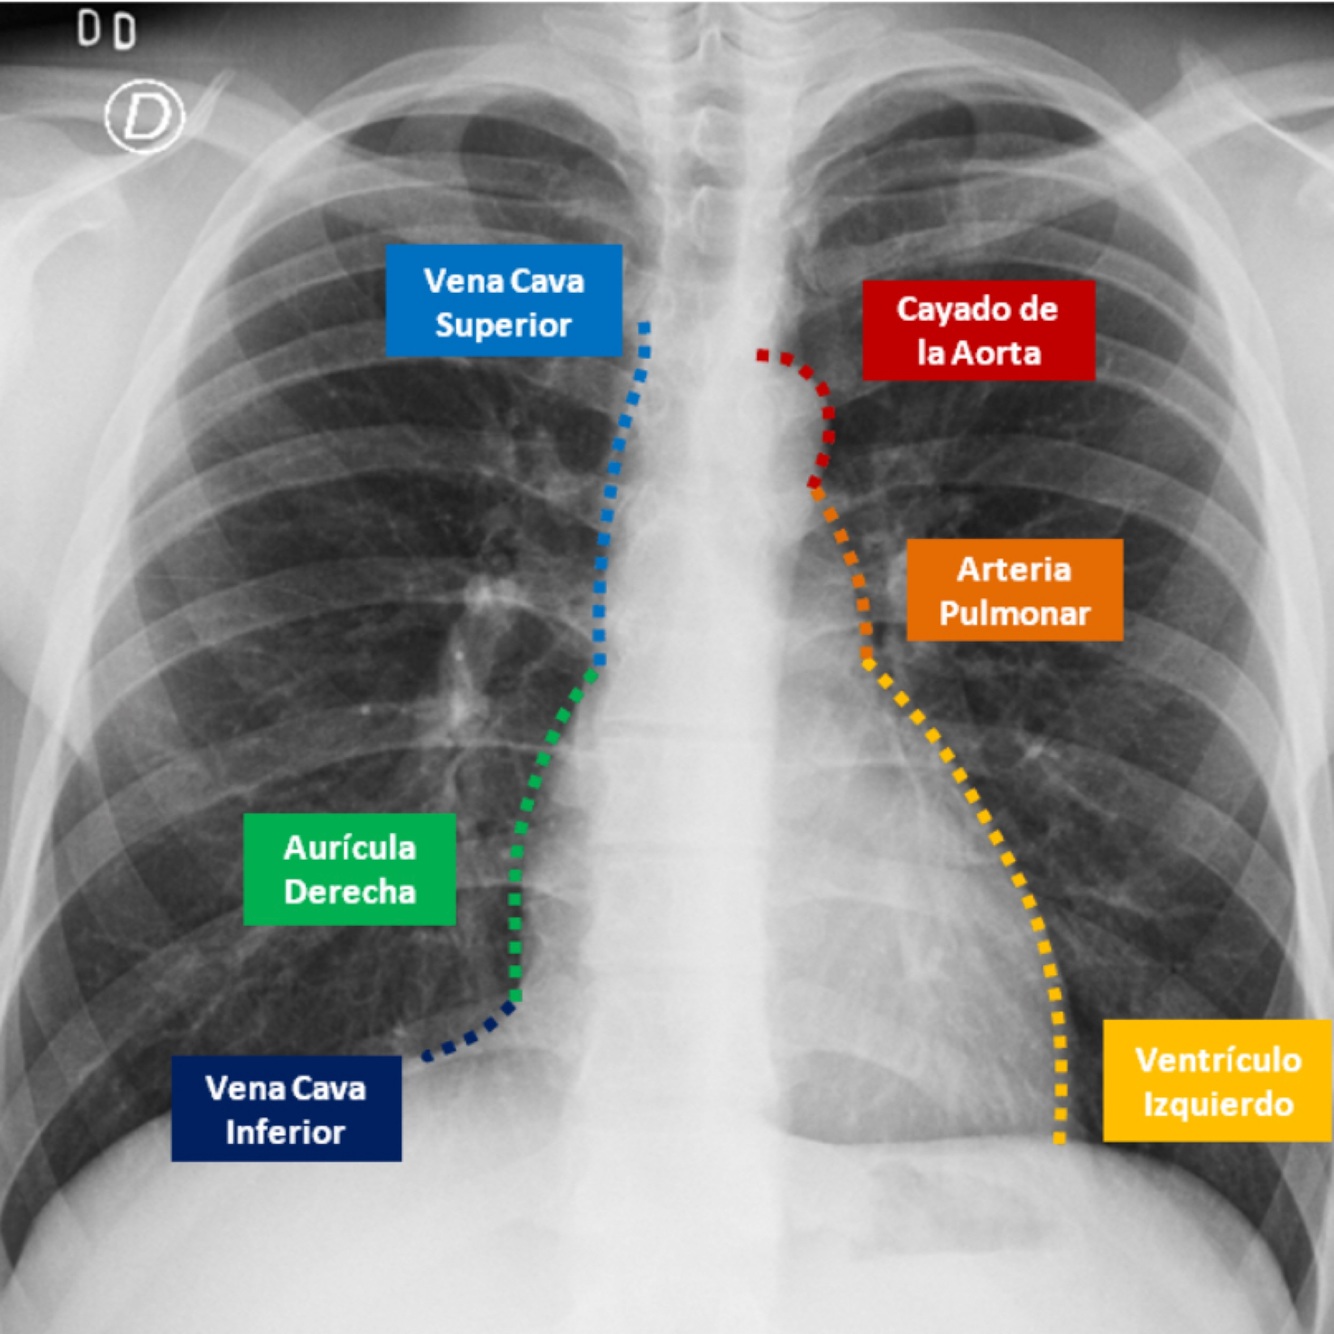

Q

Describe el perfil cardiaco

A